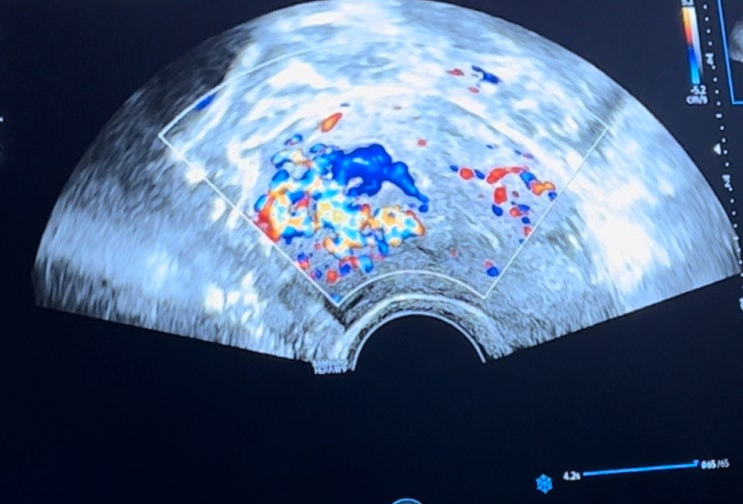

중기유산 후 태반유착, 혈관발달

유산 후 태반유착과 혈관발달도 그리 많이 있는 일은 아닌 것 같은데, 나 당첨이요.... ? < 현재 내 ...